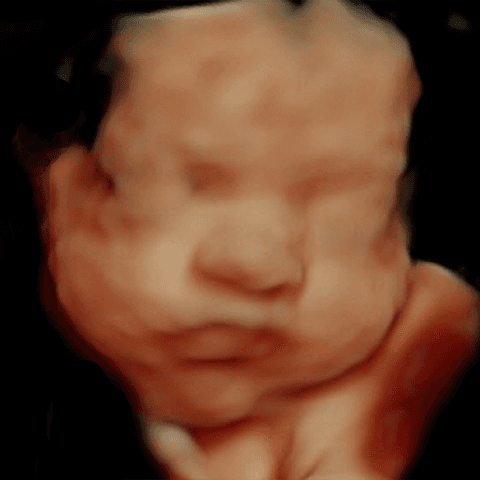

See babies, before & after

Your baby

See your baby smile in 2 minutes.

Your 3D ultrasounds stay private. Images here are shown with permission — yours will never appear on this page without your consent.